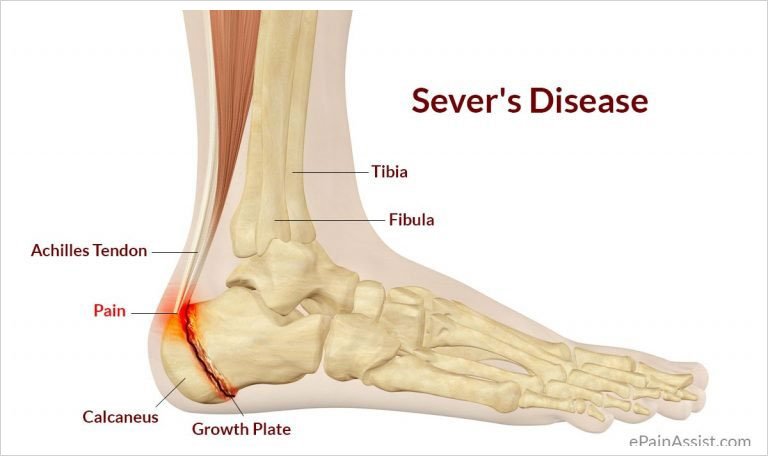

Heel Pain Causes and Treatment shop, Heel Pain Causes Diagnosis Treatment shop, 4 Heel Pain Symptoms to Take Seriously Chicagoland Foot and Ankle Board Certified Foot and Ankle Specialists and Surgeons shop, Ankle Heel Foot Pain SpinePain Solutions shop, 10 Causes of Heel Pain and When to See a Doctor Raleigh Orthopaedic shop, Heel Pain Plantar Fasciitis is a common and Painful Condition shop, Understanding Foot Pain Foot Pain Chart Foot Pain Diagram Pain Medicine Consultants Pain Specialists shop, Pain In The Back Of The Heel What Could It Mean shop, Pain In The Back Of The Heel What Could It Mean shop, Main Causes of Back of Heel Pain in North Seattle Foot and Ankle Center of Lake City shop, What Causes Heel Pain shop, Not all heel pain is Plantar Fasciitis RunningPhysio shop, Common Conditions Causing Heel Pain shop, Common Causes of Pain in the Back of the Ankles Pain Management NYC shop, Plantar Fasciitis Foot and Ankle Specialists shop, Diagnosis of Heel Pain AAFP shop, Heel pain s latest treatment techniques A Step Ahead Foot and Ankle Care shop, Ankle Heel Pain Treatment Specialists DPMC shop, Heel Pain Causes Treatment Prevention Podiatry Sydney shop, Medial Ankle Pain Tarsal Tunnel Syndrome Sports Injury Physio shop, A Stabbing Heel Pain shop, Foot Pain Conditions Causes Symptoms Treatments HSS shop, Pinpoint Your Foot Ankle Pain OrthoNebraska shop, What is heel pain Sole Podiatry shop, Foot and Ankle Pain Treatment in New Jersey RWJBarnabas Health shop, Heel Pain Causes Diagnosis and Treatment Options Joint Replacement Institute shop, Severs Disease Sever s Disease Treatment Sydney shop, Plantar Fasciitis Symptoms Causes Treatment Options shop, Ankle Pain and Plantar Fasciitis Treatment Softwave Clinics shop, Side Heel Pain What You Should Know Cellaxys shop, Foot Pain Conditions Causes Symptoms Treatments HSS shop, Effective Treatment for Heel Pain Foot Foundation shop, Heel Pain Podiatrist in Old Bridge and Sayreville NJ Jason Grossman DPM shop, Foot and Ankle Pain Treatment in Schertz BioMotion PT shop, Achilles Tendinopathy Causes Symptoms Treatment The Feet People Podiatry shop.